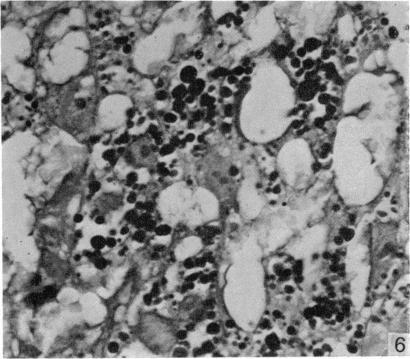

A study was made of the changes in morphology and in nuclear incorporation of tritiated thymidine in the rat uterus and placenta after ovariectomy at day 10 of gestation. There was some individual variation between different animals in the results of the ovariectomy, but in general the effects on both maternal and fetal tissues were more severe than those reported to follow ovariectomy at later stages of pregnancy. Even in the animals where there was extensive placental survival 2 or 3 days after the ovariectomy, normal differentiation of the placental labyrinth did not occur and the fetuses failed to survive. Ovariectomy had a pronounced effect on the proliferative activity of uterine epithelial cells. The high labelling index in the control animals up to day 12 was markedly reduced in the ovariectomized animals; after day 13, however, the labelling index of the controls was reduced to a level lower than that of the ovariectomized animals. Nuclear labelling occurred in the glandular epithelium from two days after ovariectomy, but was never present in the controls. There was a marked reduction in the percentage of labelled nuclei in the uterine muscle and in the metrial gland after ovariectomy. In the metrial gland this was associated with a reduction in the number of typical granulated cells and with the appearance of numerous small round cells. It is suggested that the latter represented metrial gland cell precursors which had undergone impairment of their normal differentiation process.

对妊娠第10天进行卵巢切除术后大鼠子宫和胎盘的形态变化以及氚标记胸腺嘧啶核苷的核掺入情况进行了研究。卵巢切除的结果在不同动物之间存在一些个体差异,但总体而言,对母体和胎儿组织的影响比报道的妊娠后期卵巢切除的影响更为严重。即使在卵巢切除术后2或3天仍有广泛胎盘存活的动物中,胎盘迷路也未发生正常分化,胎儿未能存活。卵巢切除对子宫上皮细胞的增殖活性有显著影响。直至第12天,对照动物中的高标记指数在卵巢切除的动物中显著降低;然而,在第13天之后,对照动物的标记指数降至低于卵巢切除动物的水平。卵巢切除术后两天,腺上皮中出现核标记,但对照中从未出现。卵巢切除术后,子宫肌层和蜕膜中标记核的百分比显著降低。在蜕膜中,这与典型颗粒细胞数量的减少以及大量小圆形细胞的出现有关。有人认为,后者代表了正常分化过程受损的蜕膜细胞前体。

Changes in the metrial gland of the rat uterus following ovariectomy on day 10 of pregnancy.妊娠第10天切除卵巢后大鼠子宫蜕膜腺的变化。

Anat Embryol (Berl). 1979 May 3;156(1):103-14. doi: 10.1007/BF00315718.